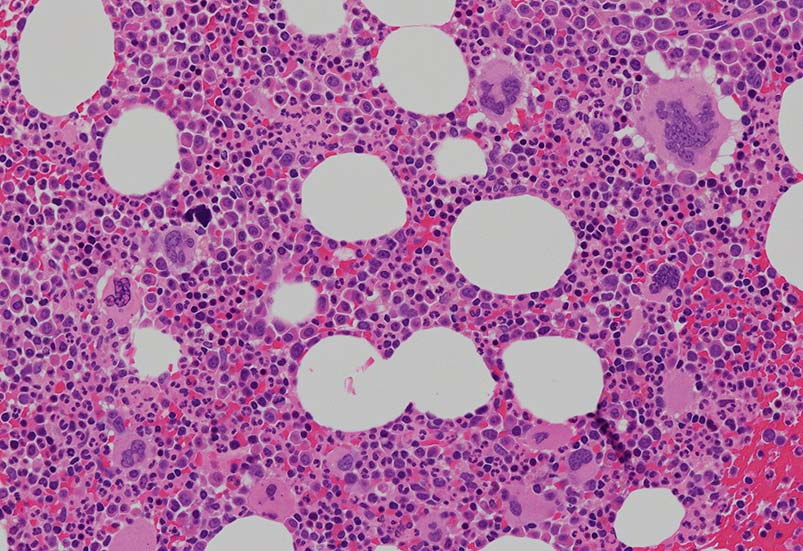

骨髄組織所見

cellularity60-70%ほどの過形成髄. ETは通常, 正形成髄から軽度の過形成髄, まれに低形成髄のこともある. 本例は軽度過形成傾向なcellularity. 巨核球数増加が目立つほか, stag-horn, cloud-likeといわれる核をもつ大型巨核球が認められる他, 小型で若い巨核球も増加している. ETでは, 連続する巨核球分化が認められる. 顆粒球系細胞増多が認められる.

Mgkの凝集所見があるが, 5-6個の緩やかな凝集で, loose clusterと呼ばれる. (Dens cluster:9個以上[数は厳密]の密なcohesiveな増殖は線維化がない場合, prefibrotic myelofibrosisの重要な所見になる)